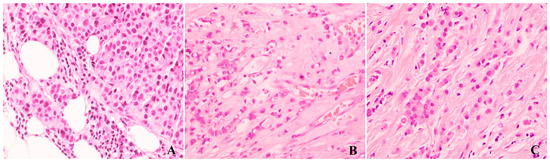

3.1. Classic Invasive Lobular Carcinoma

3.2. Histologic Variants of Invasive Lobular Carcinoma